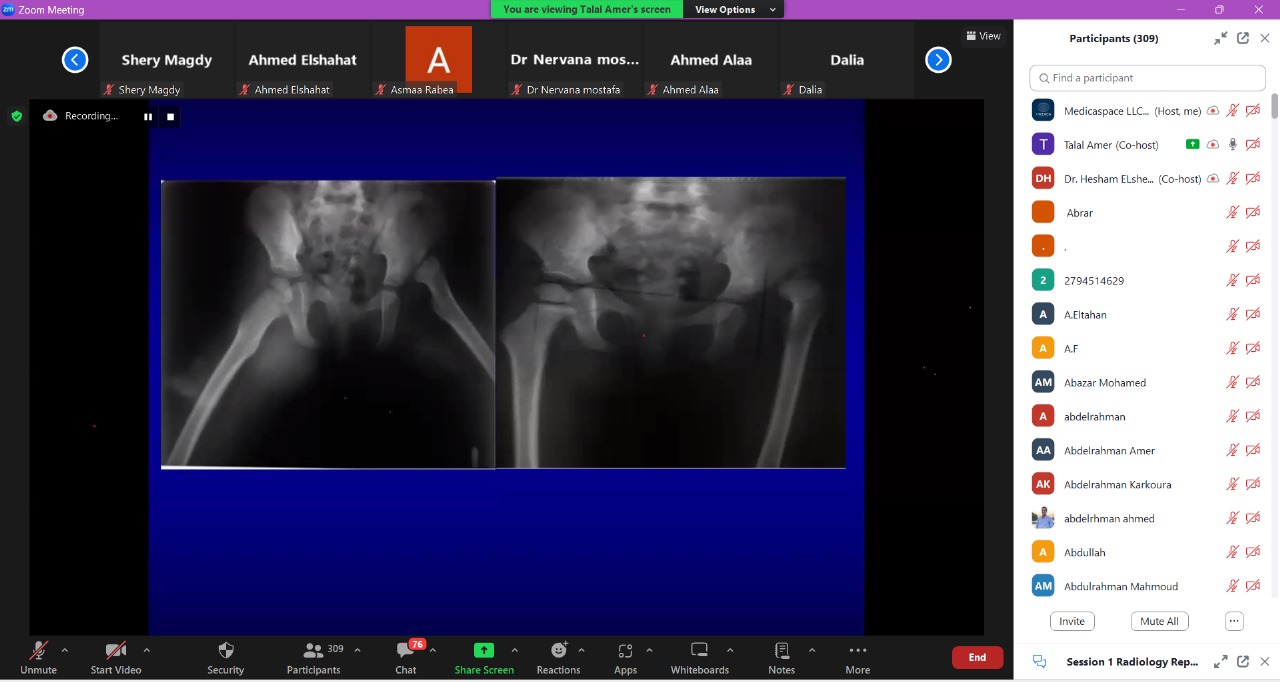

Medicaspace appreciates the effort made to make the radiology reporting course a success.

We are so proud that we are the responsible for organizing this successful course, which was attended by more than 500 individuals. With sincere thanks to the Egyptian society of radiology and all the doctors

Dr. Hesham Elsheikh

Dr. Talal Amer